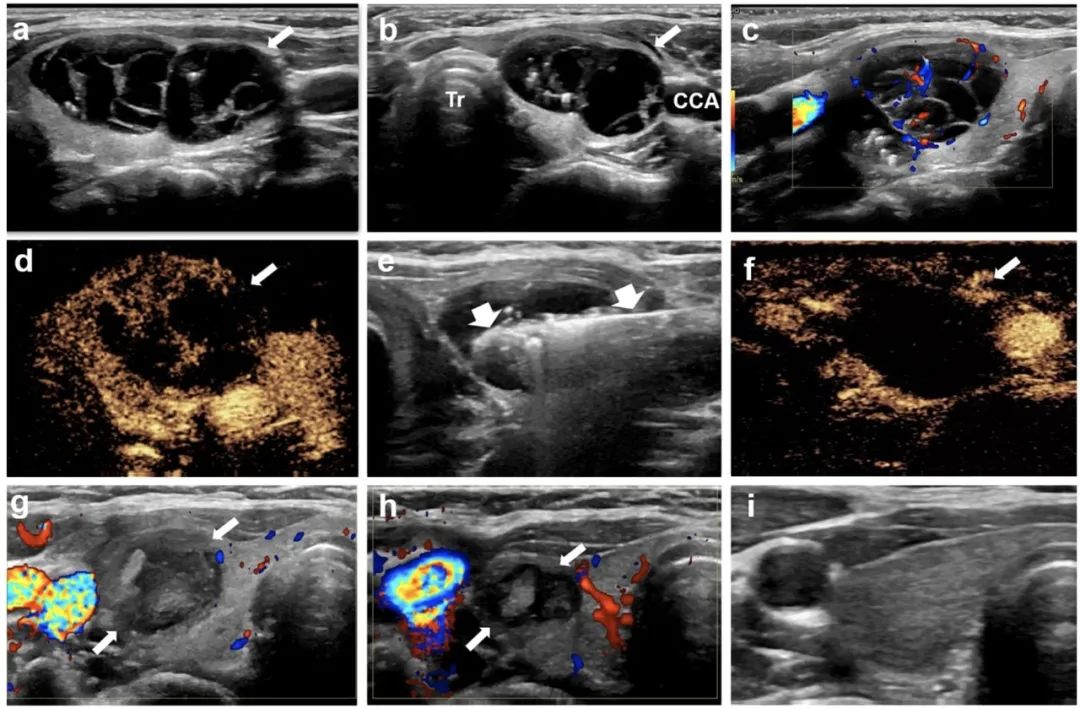

甲狀腺右葉囊性為主結(jié)節(jié),微波消融后3年,病灶完全消失